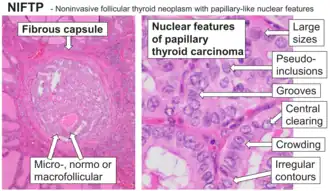

Noninvasive follicular thyroid neoplasm with papillary-like nuclear features

Definition of noninvasive follicular thyroid neoplasm with papillary-like nuclear features (NIFTP): A noninvasive neoplasm that arises from the thyroid follicular cells (cells that normally make thyroid hormone), showing a predominantly follicular growth pattern and with nuclear features of papillary thyroid carcinoma. There are several specific inclusion and exclusion criteria (see below). When these are met, this tumor has an extremely low malignant potential.[3]

1) Encapsulated or partially encapsulated. The tumors are usually very well delimited or circumscribed, with the majority encapsulated, surrounded by a well formed fibrous connective tissue capsule.

2) Complete absence of invasion of any kind in a tumor that has been thoroughly and carefully evaluated with the whole capsule of the lesion sampled.

3) Predominantly follicular pattern of growth. Papillary structures should not be present. Further, solid, insular, or trabecular architecture must be <30% of the overall tumor for this category to still apply. Colloid (the material that thyroid follicular cells create) is easily identified throughout.

4) Must have the characteristic nuclear features of papillary thyroid carcinoma, although sometimes the features are patchy in distribution without all of the tumor showing those features. The nuclear features can be divided into three main categories:

- Nuclear size and shape: nuclear enlargement, nuclear elongation, and nuclear overlapping and crowding. Loss of nuclear polarity, with nuclei at the lumen, middle, or basal zone of the cells is also a helpful finding.

- Nuclear membrane irregularities: irregular nuclear contours, nuclear grooves and folds, "rat-bites" or demi-lune formations, and the presence of intranuclear cytoplasmic inclusions.

- Nuclear chromatin characteristics: nuclear chromatin clearing, often with condensation or margination along the nuclear membranes, resulting in accentuated nuclear margins, glassy nuclei, or fine, even delicate, powdery nuclear chromatin.